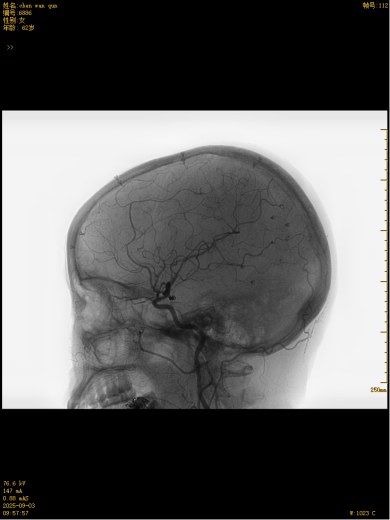

这款国产创新技术的优势不止于疗效:通体显影设计让支架定位精准到毫米级;超弹性材质与优化编织工艺实现极致贴壁,兼顾支撑力与柔顺性,适配复杂迂曲脑血管;操作更轻巧、创伤更小,仅需大腿根部米粒大小切口即可完成手术,可实现患者术后可快速康复。本次手术中,团队在DSA引导下精准释放支架,全程耗时短、出血少,术后造影显示,动脉瘤内血流即刻变得迟缓,载瘤动脉通畅,重要分支血管保护完好。患者术后恢复良好,未出现任何神经功能障碍,术后不久即快速康复出院,重获健康,恢复正常生活工作。